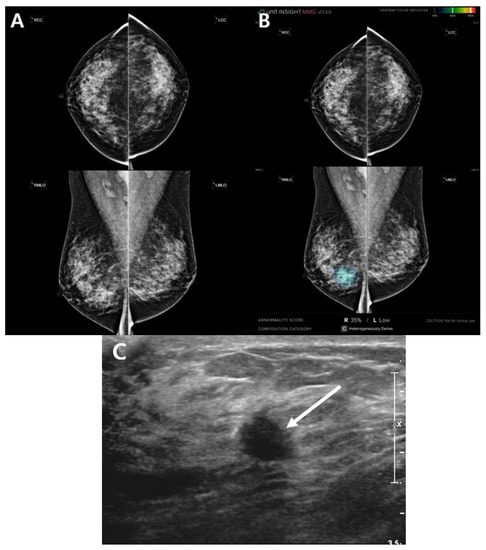

| Case No. | Age (Year) | Symptom | MG Density | AI Score (%) | Lesion Location |

|---|---|---|---|---|---|

| A1 | 35 | Palpation | d | 14.48 | L |

| A2 | 49 | Other | c | 35.46 | R |

| A3 | 46 | Palpation | c | 30.86 | L |

| A4 | 42 | Palpation | c | 24.49 | L |